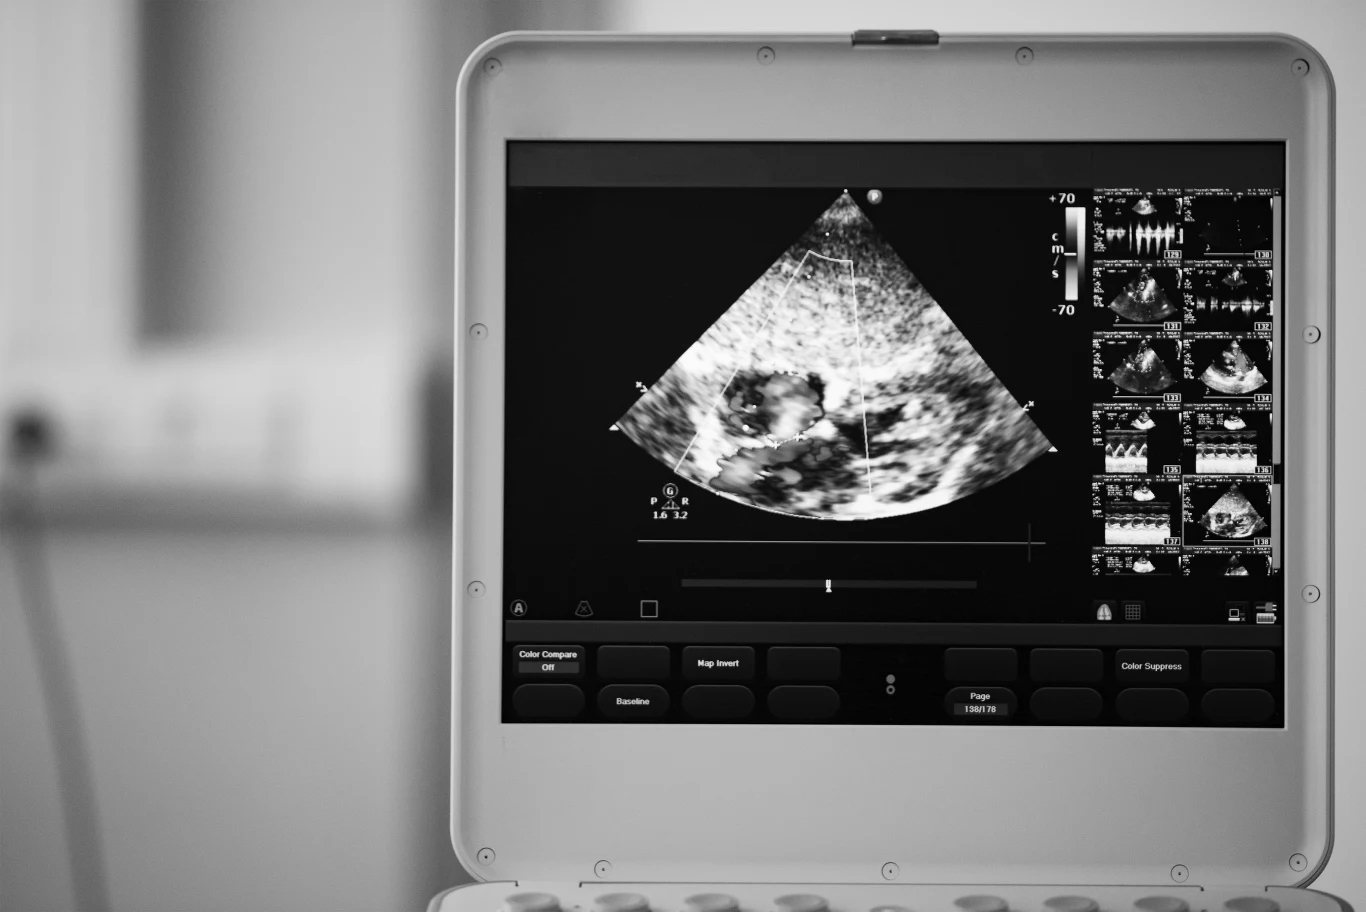

Echokardiografia (echo serca, UKG) polega na ocenie struktury i działania serca za pomocą aparatu ultrasonograficznego (USG). Urządzenie to umożliwia bezinwazyjny podgląd jam serca (komór i przedsionków), zastawek naturalnych i sztucznych, grubości ścianek serca. Za pomocą aparatu USG lekarz ocenia objętość jam serca oraz ich kurczliwość.

Echokardiografia pozwala także stwierdzić ewentualną obecność skrzepów w jamach serca i płynów (np. krwi) w worku osierdziowym (worek otaczający serce). Badanie przepływu krwi w jamach serca i naczyniach krwionośnych nazywa się echokardiografią dopplerowską.

Echokardiografię zwykle wykonuje się przezklatkowo (przez ścianę klatki piersiowej).